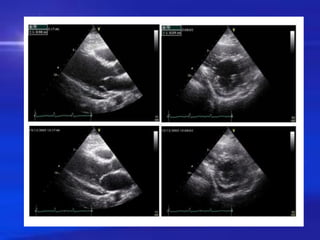

TRAØN DÒCH MAØNG TIM

❖ SIEÂU AÂM :

Möùc ñoä traøn dòch :

– Löôïng nhoû : khoaûng troáng sieâu aâm < 10 mm (taâm

tröông )

– Löôïng vöøa : ít nhaát ≥ 10 mm ôû thaønh sau

– Löôïng lôùn : ≥ 20 mm vaø cheøn eùp tim

TDMNT LÖÔÏNG LÔÙN

◼

TDMNT LÖÔÏNG VÖØA

TDMNT DO VIEÂM